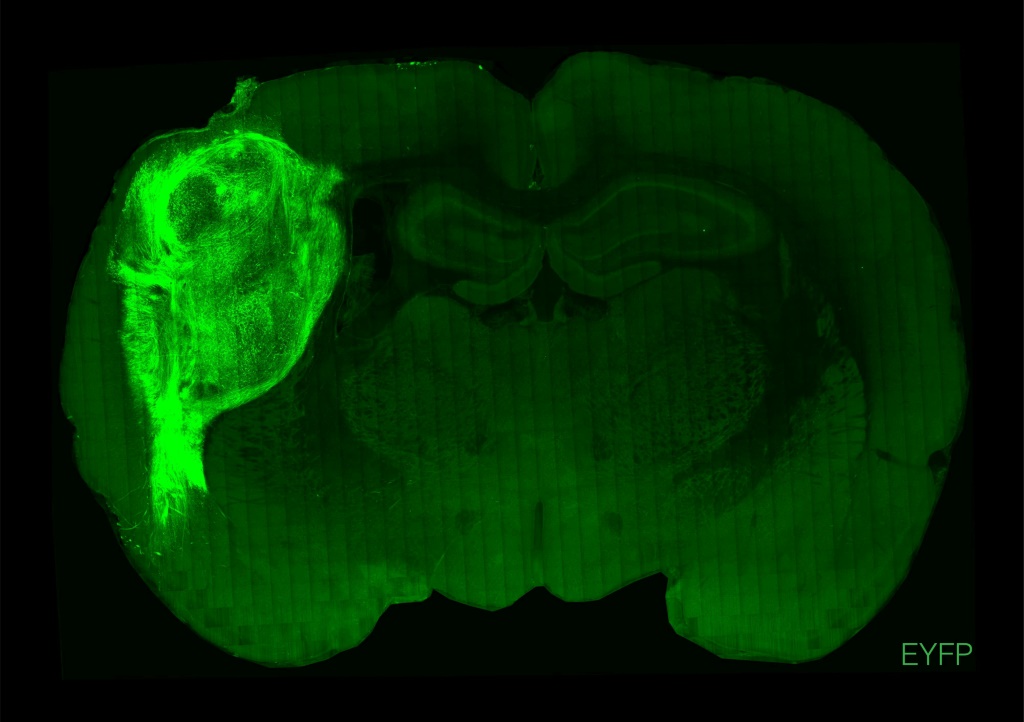

ويشرح البروفيسور باسكا أنه من خلال زرعها في حيوان صغير، "وجدنا أن العضويات يمكن أن تصبح كبيرة جداً وذات أوعية دموية"، وبالتالي يمكن مدها بشبكة الدم الخاصة بالفأر، إلى درجة "احتلال حوالي ثلث مساحة نصف الكرة المخية".